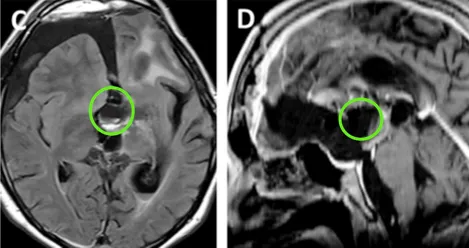

术后情况:术后MR提示肿瘤几乎全切,两个大脑前动脉A2断动脉血管区域灌注正常,视交叉和视神经束、垂体柄和下丘脑保持原样。